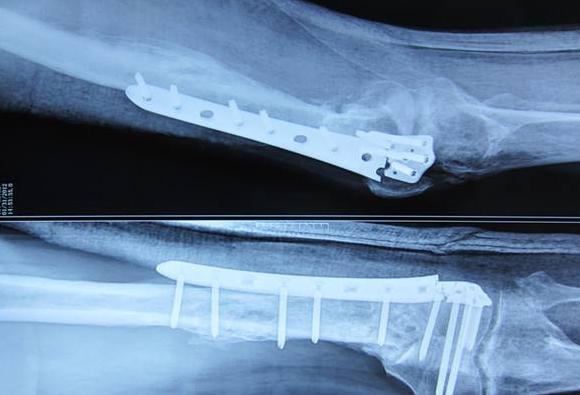

影像学检查 X线仍然是骨折愈合评估的主要内容。相关研究表明,髋关节放射*联学**合评分(RUSH)和胫骨放射*联学**合评分(RUST)这两项评分系统,可提高外科医师和放射科医师对于骨折修复的评判。通过使用这些新的评分系统,评估愈伤组织桥接的皮质数量具有更高的可靠性。计算机断层扫描(CT)在评估骨折线的愈合和可视化方面优于普通X线。超声波比放射线照相能在更短的时间内正确预测骨折愈合情况。通过结合MRI的优越软组织成像和PET的半定量代谢放射性示踪剂摄取率,18FPET-MRI成像显示出作为评估骨折愈合的技术前景。

提供稳定的机械环境 在骨折和延迟愈合动物模型中,髓内钉动力化能改善骨愈合,有作者推荐将髓内钉动力化作为长骨干骨折髓内钉治疗的标准程序,可作为一线手术治疗推荐。髓内钉动力化的基本原理是增强骨折部位微动,刺激愈合。同时使用更长的髓内钉能够更好地填充整个髓内管和使用更多的锁定螺钉也有助于稳定生物力学结构。迄今为止,动力治疗的最佳时机尚不明确,但骨折延迟愈合的动力治疗比骨不连的动力化治疗效果更好。在无菌性骨不连治疗方面,无菌胫骨轴扩髓内钉治疗骨不连愈合率高(97%)。